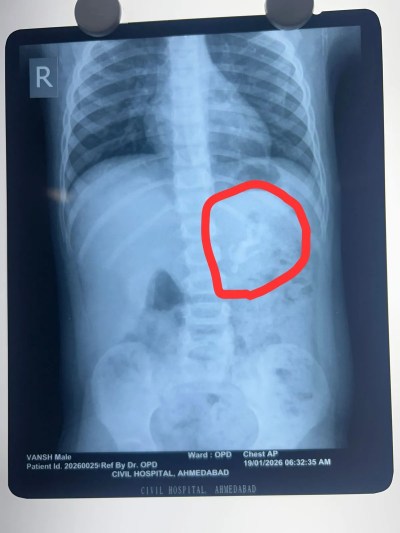

Ahmedabad: शहर स्थित सिविल अस्पताल में चिकित्सकों ने जटिल ऑपरेशन कर डेढ वर्ष के एक बच्चे के पेट से प्लास्टिक का खिलौना निकाला।बताया जाता है कि शहर का एक बच्चा खेलते-खेलते प्लास्टिक का खिलौना निगल गया था। बच्चा खेलते समय अचानक उल्टी करने लगा और उसके चेहरे पर तकलीफ के भाव दिखे। बच्चे की मां को शंका हुई कि बच्चा कोई वस्तु निगल गया है। जांच करने पर पता चला कि खिलौनों में से एक गायब है। परिवार तत्काल उसे शहर के सिविल अस्पताल लेकर पहुंचा। अस्पताल में एक्स-रे में पूरा खिलौना जठर में फंसा दिखाई दिया। चुनौती यह थी कि अन्ननली और जठर के बीच से इतने बड़े खिलौने को सुरक्षित बाहर कैसे निकाला जाए।

अस्पताल के चिकित्सा अधीक्षक एवं पीडियाट्रिक सर्जरी विभागाध्यक्ष डाॅ. राकेश जोशी ने बताया कि एंडोस्कोप के नाजुक उपकरण से खिलौने को पकड़ने का प्रयास करते समय वह बार-बार फिसल रहा था। यदि इसे ज्यादा जोर से खींचा जाता तो वॉल्व को स्थायी नुकसान हो सकता था। अंत में सावधानी से खिलौने के सिर वाले हिस्से को पकड़कर वॉल्व पार कराया गया और बाहर निकाला गया।

डॉक्टरों का कहना है कि यदि यह खिलौना जठर से आगे आंतों में चला जाता तो ब्लॉकेज और आंत फटने का खतरा था। समय पर अस्पताल पहुंचने और चिकित्सकों की कुशलता से बच्चे की जान बच गई। इस जटिल एंडोस्कोपिक सर्जरी में एनेस्थीसिया विभाग की डॉ.श्वेता व उनकी टीम ने सहयोग किया। ऑपरेशन के बाद बच्चा पूरी तरह स्वस्थ है।